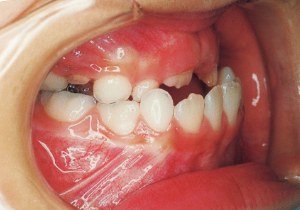

Age at Initial Visit: 8 years 1 month, Female / Protruding lower bite. Protruding lower jaw

1 Initial Visit 8-29-’79

Although there were many missing deciduous teeth, the number of permanent teeth was not problematic (4). The amount of negative overjet was significant (1). On cephalometric radiographs, the mandibular ramus was not relatively long, but the large gonial angle and the long mandibular body were noticeable, indicating an overall tendency of the mandible to project inferiorly and anteriorly. High lower facial height was also characteristic.

A potential predisposition to mandibular protrusion was clearly evident.